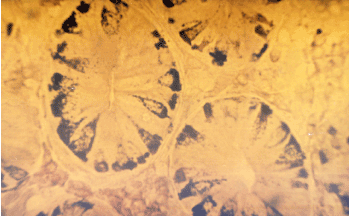

Figure 1 Helicobacter pylori B gastritis. Gimsa x 300.